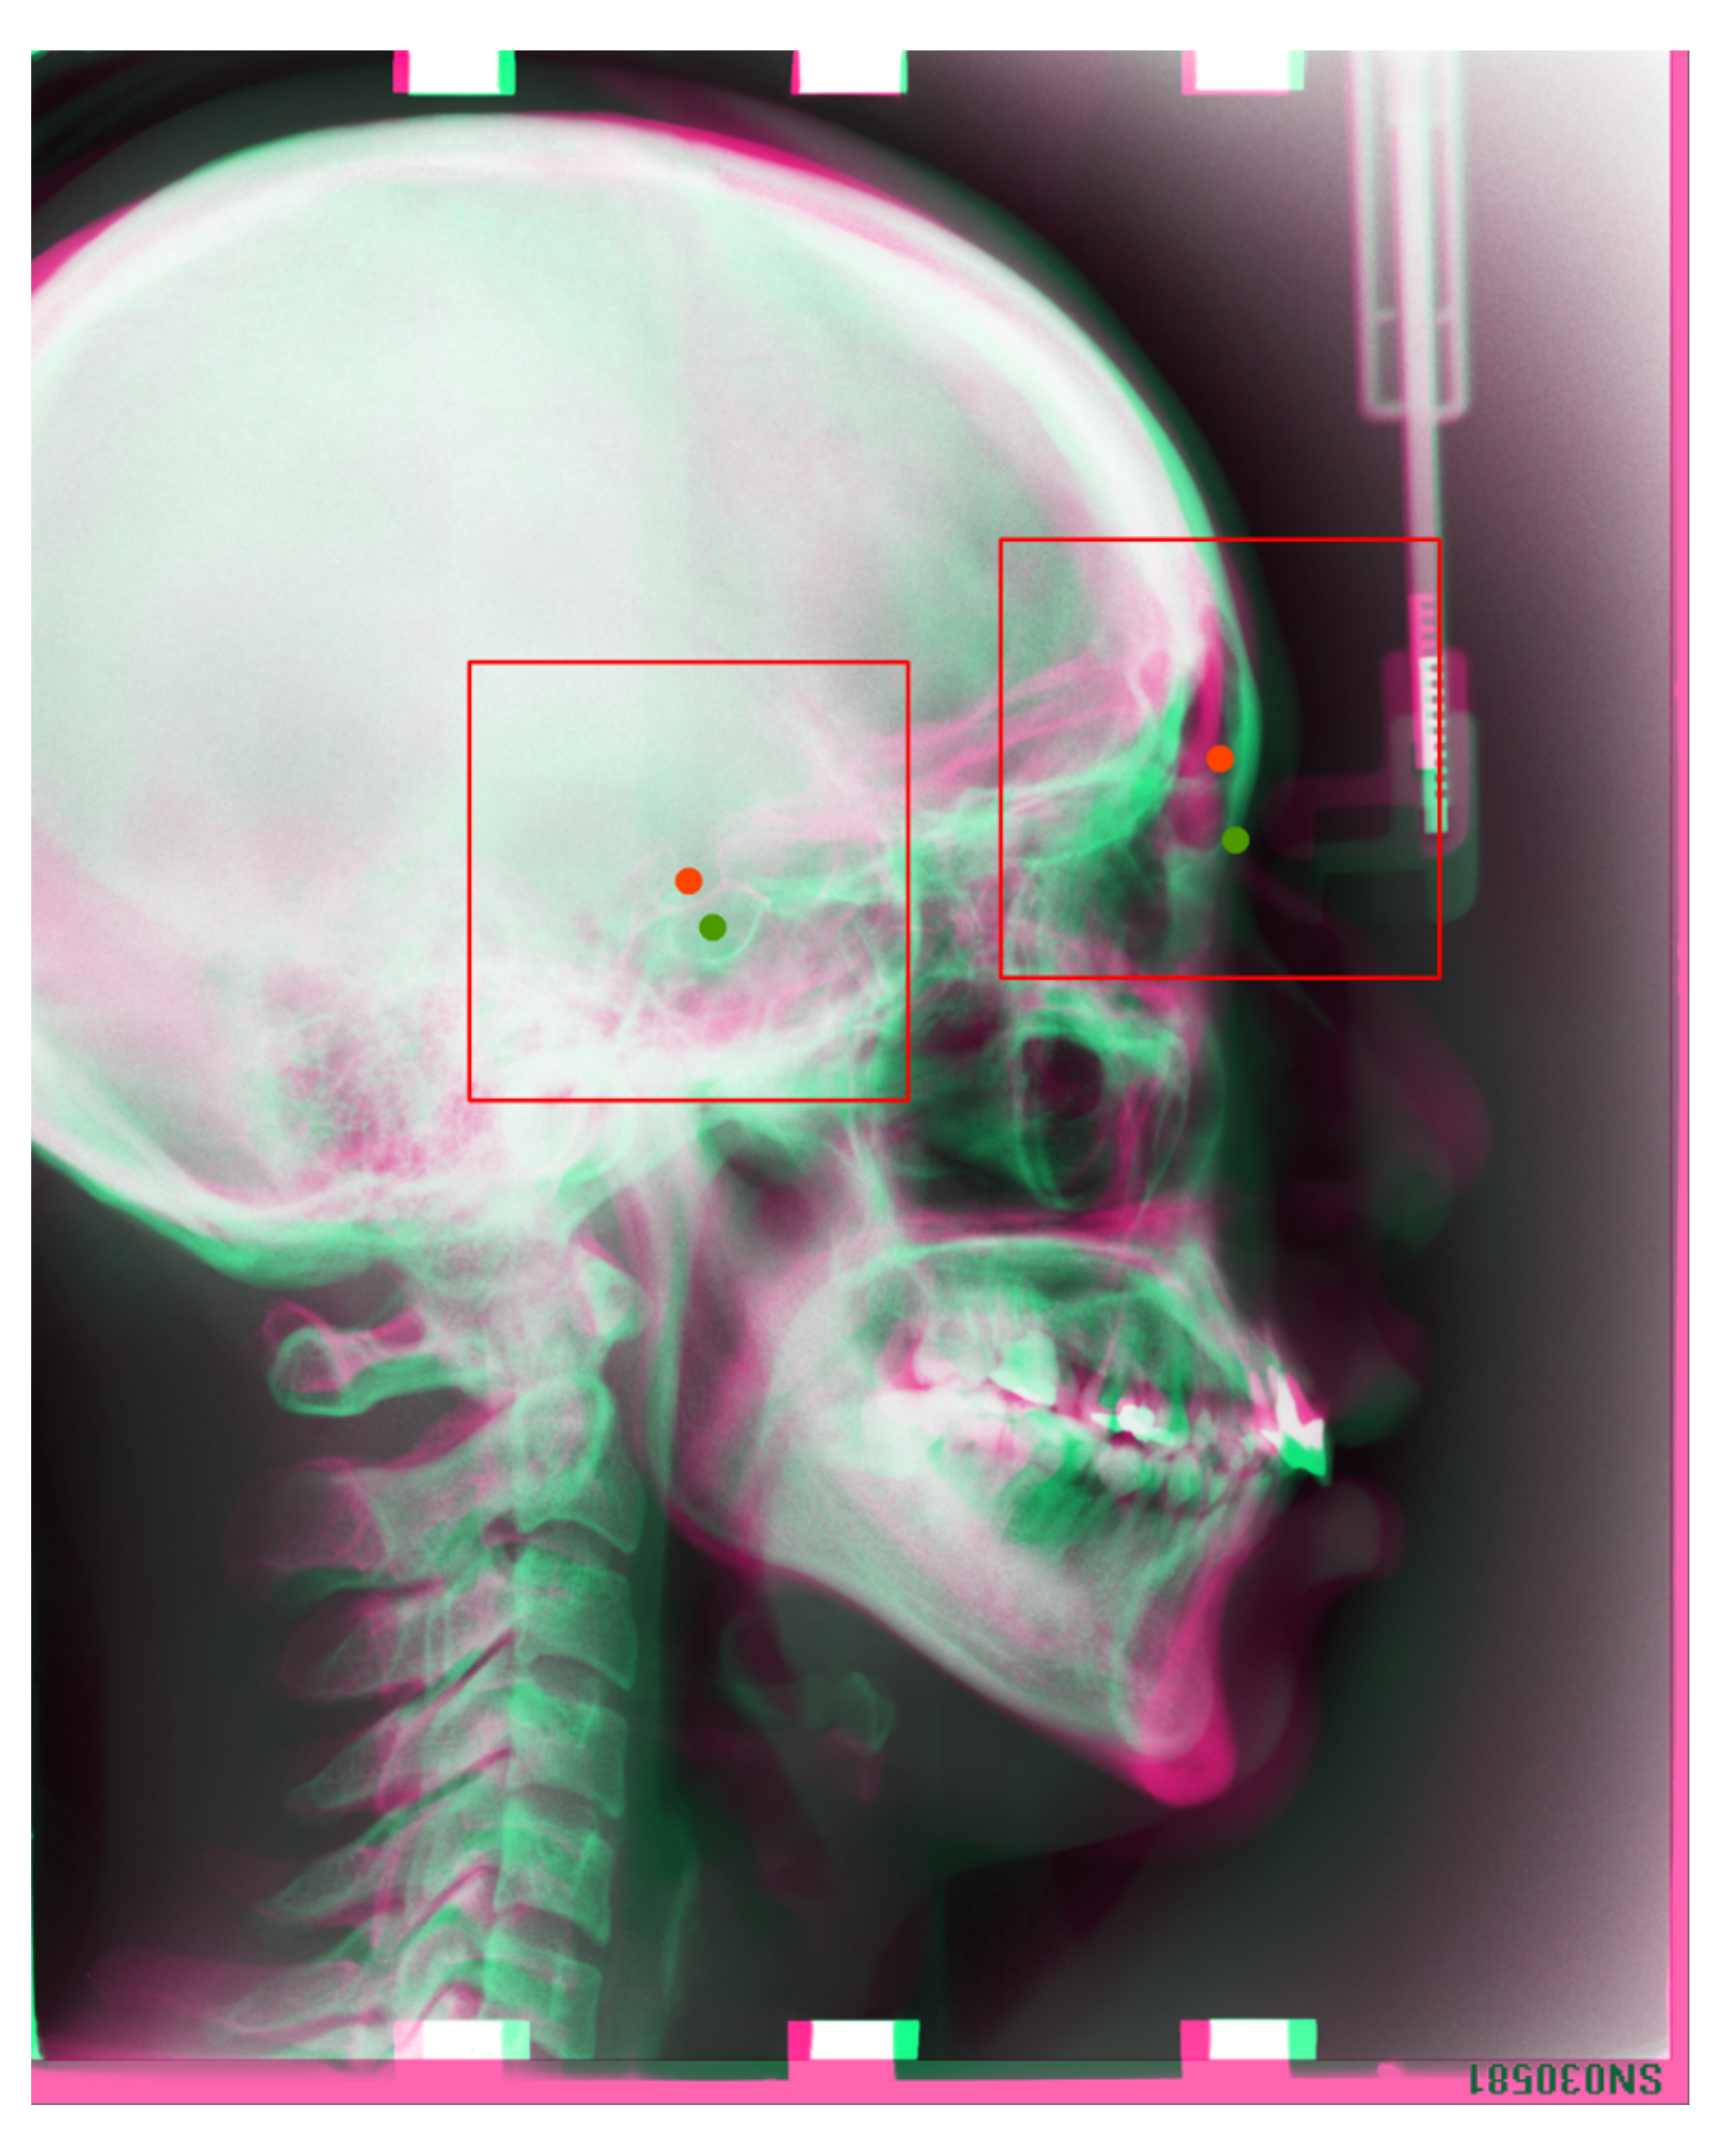

After registration, we copy the landmark locations of the reference images (training images) to moving images (test images). We consider the landmark location of a reference image as the center of the ROI patch, extract a 512 × 512 resolution patch image on the moving image, and then resize it to a 256 × 256 resolution patch for the test. The extracted images will be treated as input to our trained convolutional neural network (CNN); thus, we can detect the corresponding landmark in the patch image. The registration results are presented in Figure 5.

Figure 5. In the image, we take the reference image’s landmarks(Training images) as center of the patch image, then we draw a bounding box (ROI) in the test image, as the input to our corresponding trained models. Red dots are the reference images’ landmarks, green dots are test image’s landmarks, which are the landmarks we aim to detect.